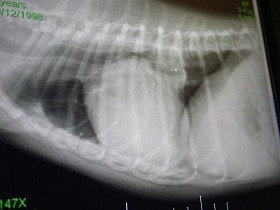

レントゲンを見ながら先生が、

『携帯で写真とか撮ってもいーよ。』って言ってくれてね。

持参していた一デジさんで撮影させていただきました。

コレね。

上↑の写真と全く同じなんですけど・・

今迄、レントゲンを見せてもらってても、

白くハッキリと確認できる部分だけが心臓なんだと思ってたらね

赤く色付けした部分は肥大してしまってるところだよ。って教えてもらってね。

(ちょっと大袈裟に書きすぎたかも^^; )

黄色は気道です。

・・そりゃ。咳・・出るわぁ・・(T▽T;)

気道を圧迫どころか、重なるように押し上げてる状態だものね・・。

レントゲン1枚にしても 何って分かりやすいんでしょう・・。